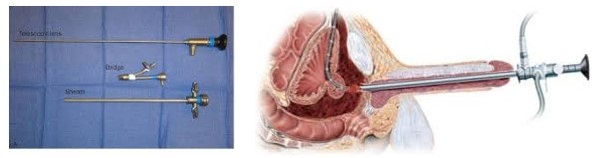

4. urethroscopy:

That is performed in the operating room by a urologist, and the entire urethra is seen by the phycisian through the bladder area with the endoscopic device.